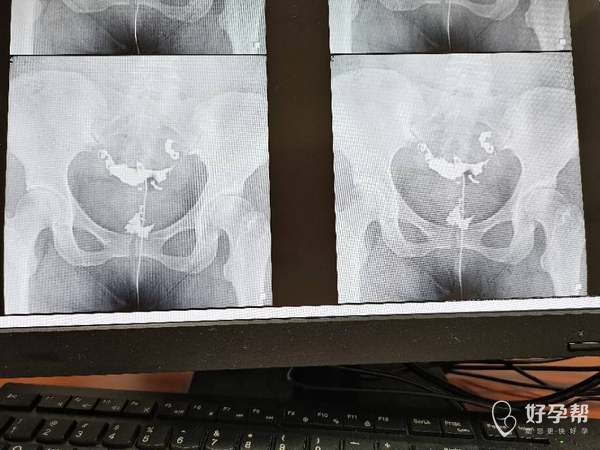

请问造影片子上能看出是输卵管哪里堵塞吗做腹腔

从片子看你这个是输卵管远端阻塞,做宫腹腔镜联合手术效果比较好